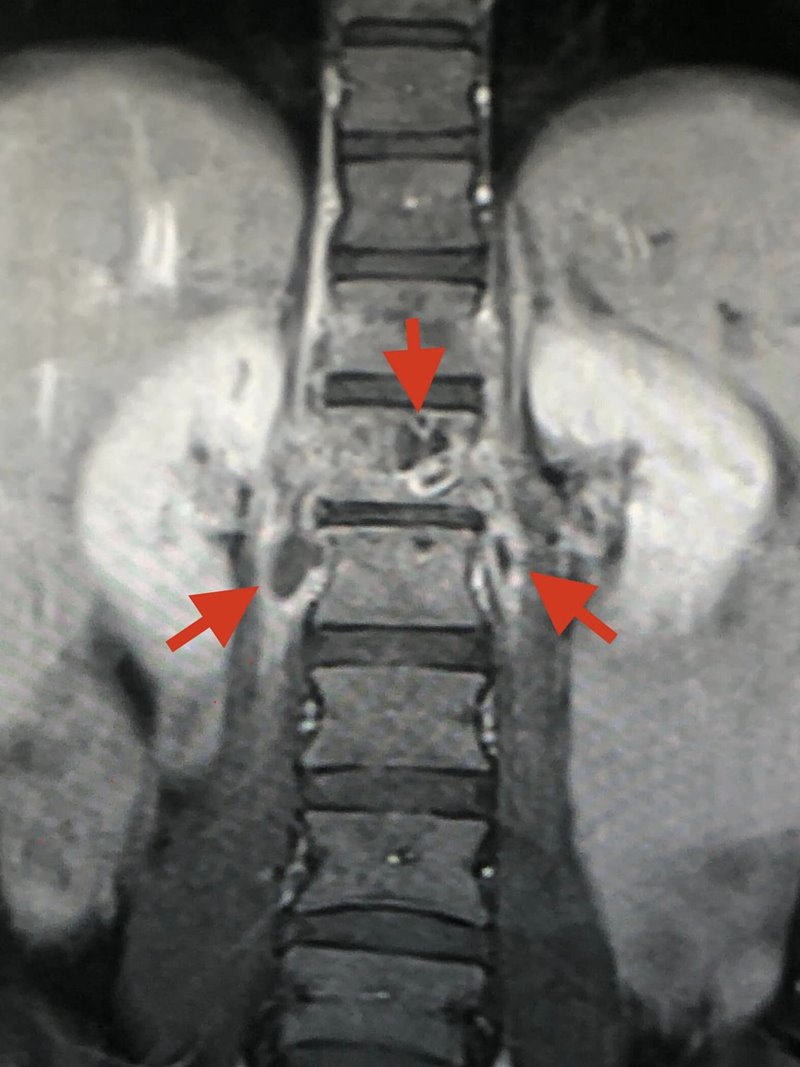

อย่างไรก็ตาม เมื่อลองทำ MRI กระดูกสันหลังส่วนเอว กลับพบความผิดปกติ และมีความเป็นไปได้ที่เธอจะเป็นวัณโรคของกระดูกสันหลังส่วนเอวชิ้นที่ 1 และสงสัยว่าจะมีการอักเสบรอบ ๆ เนื้อเยื่อกระดูกสันหลังส่วนเอวชิ้นที่ 1 และ 2 ร่วมด้วย จึงทำการเจาะเนื้อเยื่อรอบกระดูกสันหลัง ส่งตรวจย้อมเพื่อหาเชื้อวัณโรค และให้ผลลบ จากนั้นก็รอเพาะเชื้อวัณโรค ส่งตรวจพยาธิวิทยา พบว่าเนื้อเยื่อตายและไม่พบมะเร็ง และสรุปได้ว่า เธอเป็นวัณโรคที่กระดูกสันหลัง

ภาพจาก เฟซบุ๊ก หมอมนูญ ลีเชวงวงศ์ FC